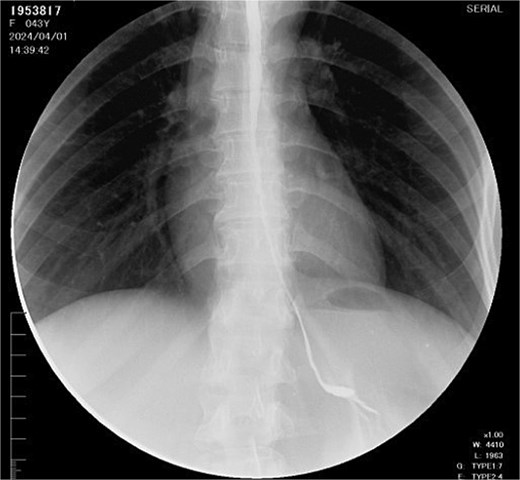

The right colon was mobilized using a standard Cattell–Braasch maneuver. Intraoperative assessment revealed the absence of the right colic artery; perfusion relied on the ileocolic artery and the right branch of the middle colic artery via a well-formed marginal artery of Drummond (Fig. 2). Temporary occlusion of the ileocolic vessels confirmed adequate collateral flow (Fig. 3). The terminal ileum was transected ~3 cm proximal to the ileocecal valve, and an incidental appendectomy was performed.